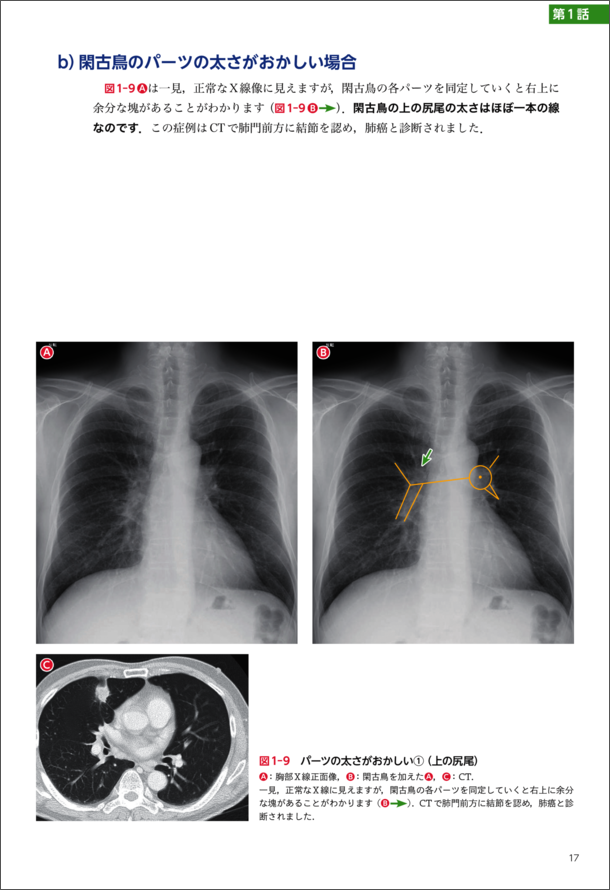

『第1話 肺門編「閑古鳥を探せ!」』より抜粋